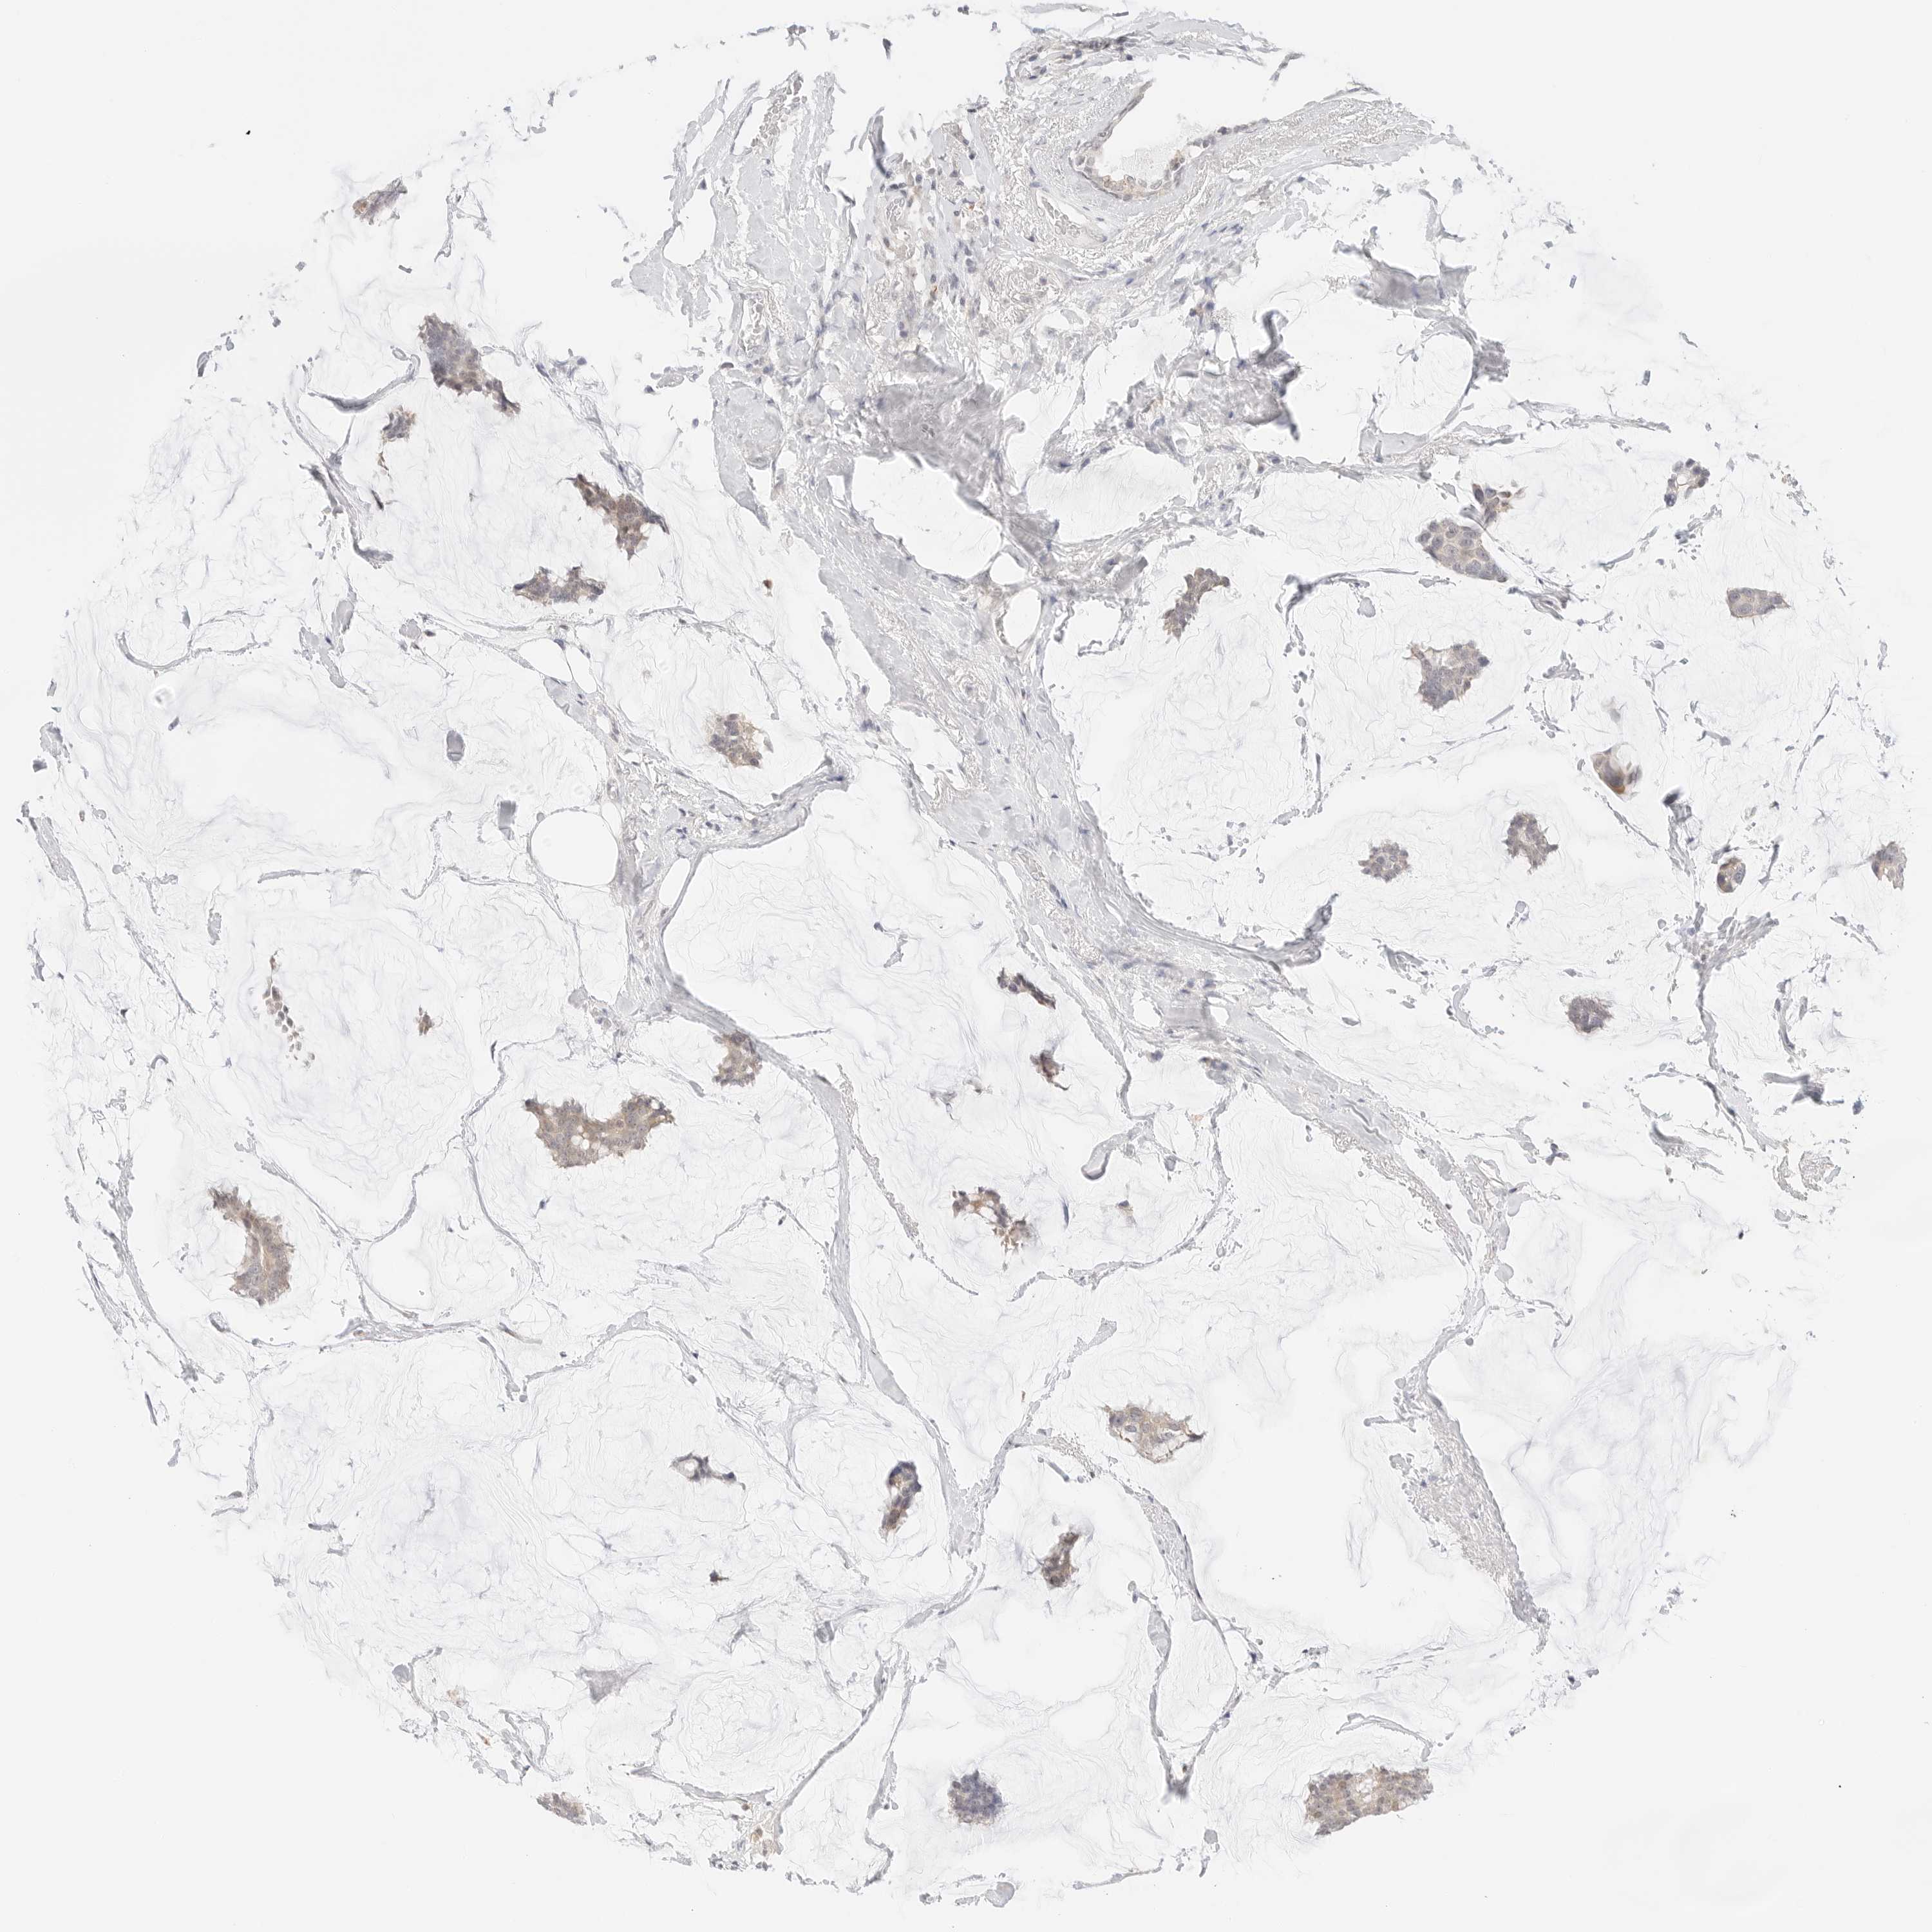

CANCER BREAST CANCER Show tissue menu

BRCA TCGA BRCA VALIDATION PROTEIN EXPRESSION